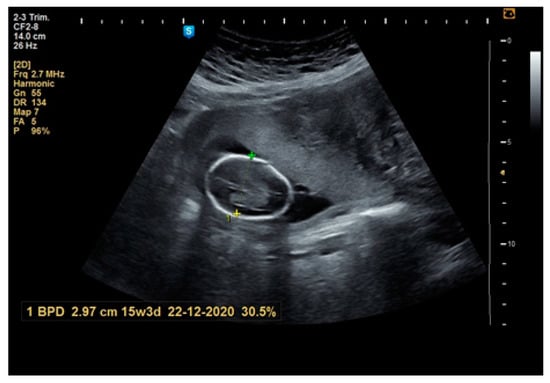

| before pregnancy during pregnancy | 26 (45.6) 31 (54.4) | 4 (33.3) 8 (66.7) | 18 (48.6) 19 (51.4) | 2 (50) 2 (50) | 2 (50) 2 (50) | 0.8184 |

| Antepartum | 1st Trimester | 2nd Trimester | 3rd Trimester | |

| N | 55 | 49 | 50 | 53 |

| Mean | 40.02 | 44.51 p = 0.005 * | 54.76 p = 0.001 * | 61.58 p = 0.001 * |